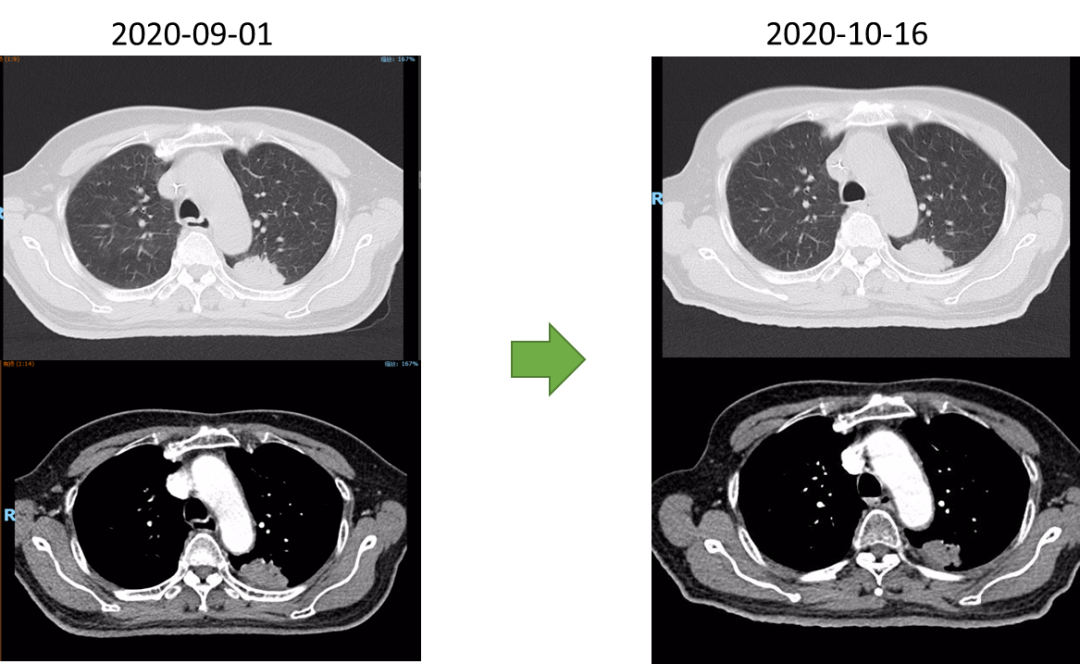

疗效评估及随访

放射治疗结束复查胸部CT:左肺上叶尖后段与左肺下叶背段交界处病灶较前略显缩小,现最大横断面约2.6*2.8厘米,边缘可见毛刺,增强后可见强化,邻近胸膜稍增厚。食道中段管壁增厚,上下累及约4.5厘米(约胸5/6椎间隙水平至胸8椎体上缘水平),增强后强化程度似较前有所减低,隆突下见境界不清淋巴结。

2021-10-28外院PET-CT:原食管胸下段管壁高代谢灶较前缩小,放射性较前减低,现大小约15×17×17mm,SUVmax 3.1,考虑为治疗后改变。左肺上叶团块状高代谢灶较前缩小,放射性摄取较前减低,现大小约25×18mm,SUVmax 2.1,考虑为治疗后改变。